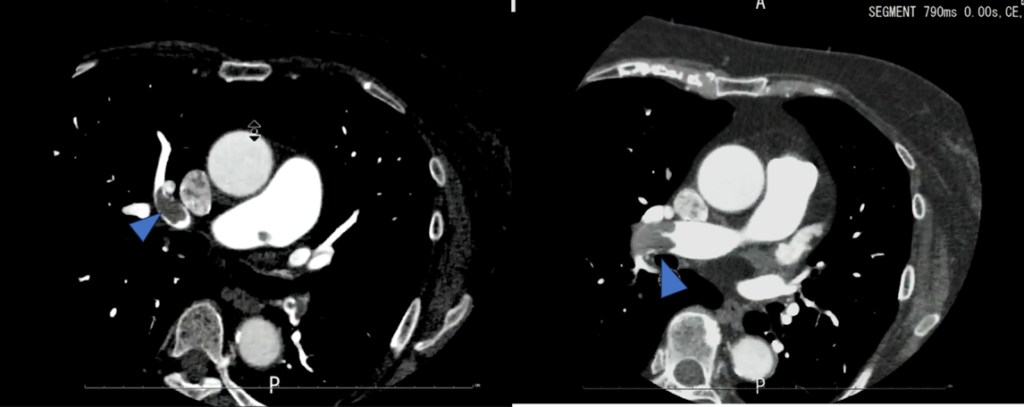

上行動脈にROIを置いたボーラストラッキングにてイオパミロン370 造影剤注入速度5.0ml/sec 造影剤量65mlにて撮影された画像です。

両側の肺動脈に造影不良域(filling defect)を認めます。

肺動脈塞栓(PTE)を疑う画像です。

この症例では撮影者がリアルタイムにこの所見に気づき、すぐ放射線科医に報告し肺動脈と深部静脈を観察するために胸腹部の追加撮影を行いました。

(当院では造影CTを行う際に放射線科医も同席するためその場で確認することができ、撮影を追加しました。本来であれば残った造影剤を全部注入し肺動脈の検査と深部静脈の検査を行う方が良かったのですが、腎機能も低かったのでこのまま撮影することとなりました。その際、少しでも造影効果を高めるために管電圧を80~100kVに下げて撮影を行いました)

その時の画像がこちらです。

造影後3分で追加撮影をしました。

この方は検査前情報にはなかったのですが、右のTKA術後の方でした。右膝関節術部周囲を主体に下腿~大腿骨遠位レベルにfilling defectが複数認められました。

管電圧を下げて撮影することで、造影剤が60mlほどでも深部静脈の評価が可能でした。時間経過で造影効果が低くなった肺動脈の観察も観察することができました。